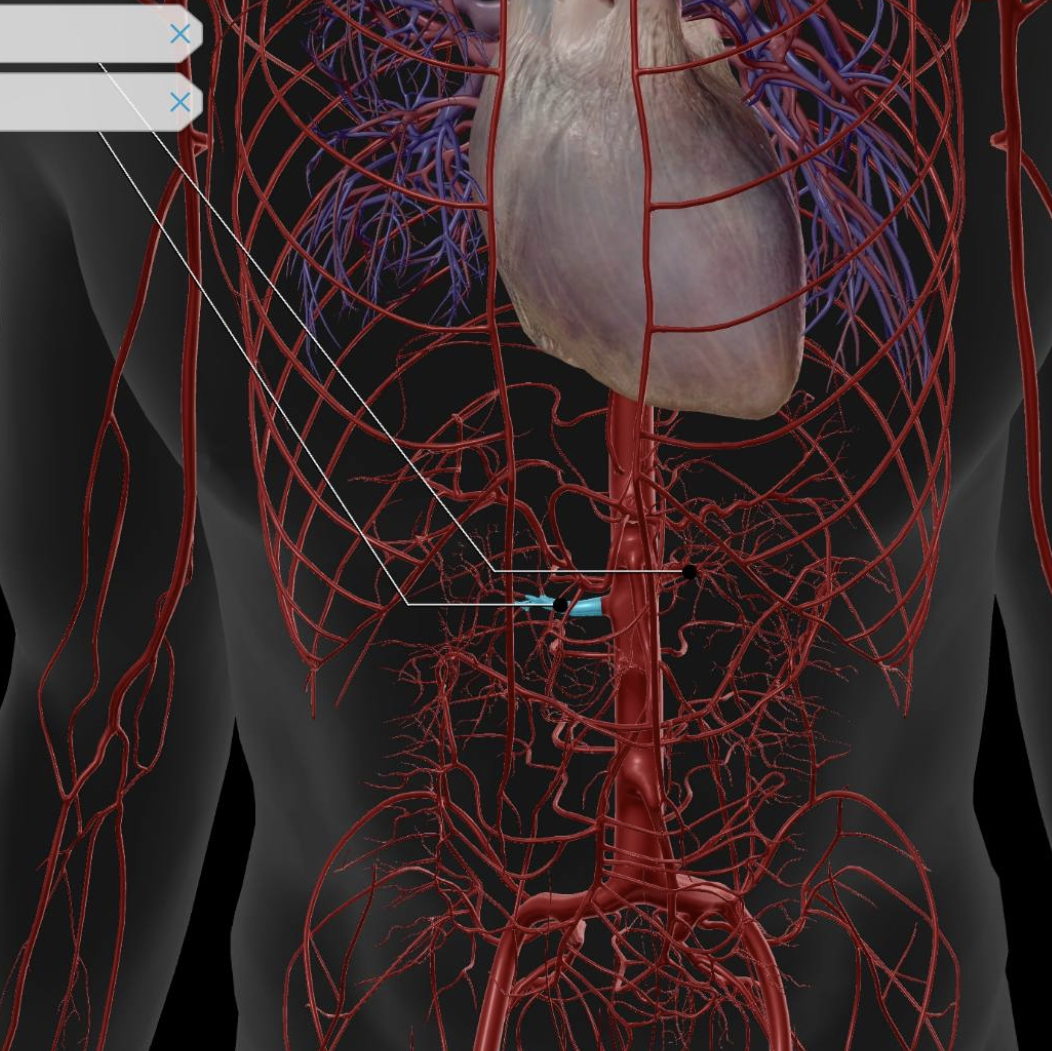

Abdominal Aorta

Superior Mesenteric Artery

Inferior Mesenteric Artery

Renal Artery

Common Hepatic Artery

Celiac Trunk